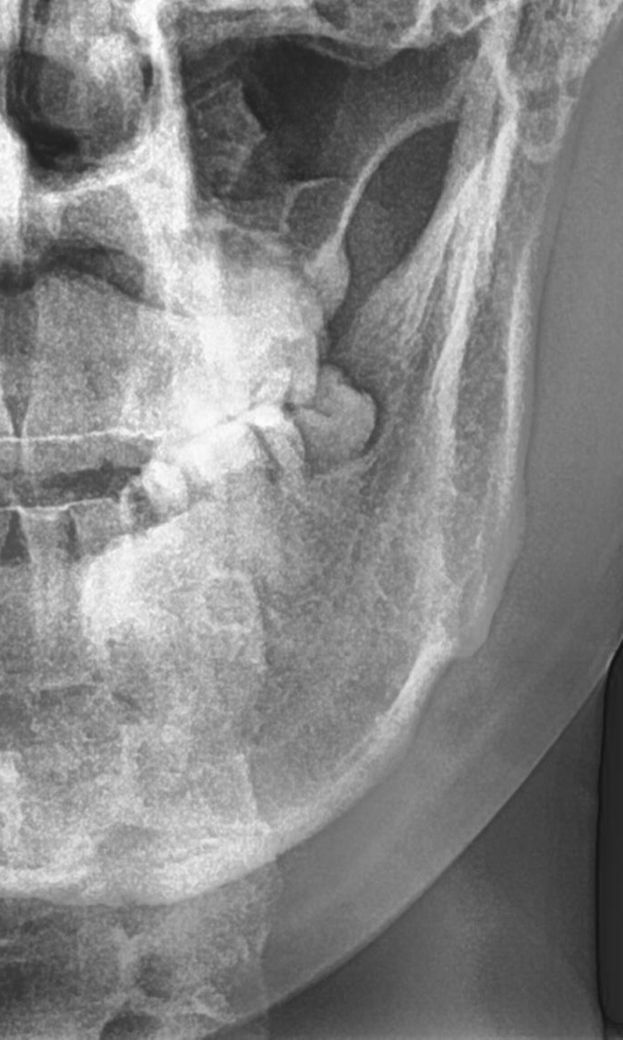

사진은 사랑니 뽑기 전

• 2번 째 사진

• 안녕하세요 치과의사 김철진입니다. 사진상으로 보면 단순 발치엿을꺼 같습니다. 아직 마취가 안풀린게 아닐까 생각되니 너무 걱정하지마세요.

1. 사진상 신경이 사랑니와 아주 가깝진 않습니다.

2. 특별히 발치 중 무리한 기구동작이 없었다면 신경을 건드리진 않았을 것 같습니다.